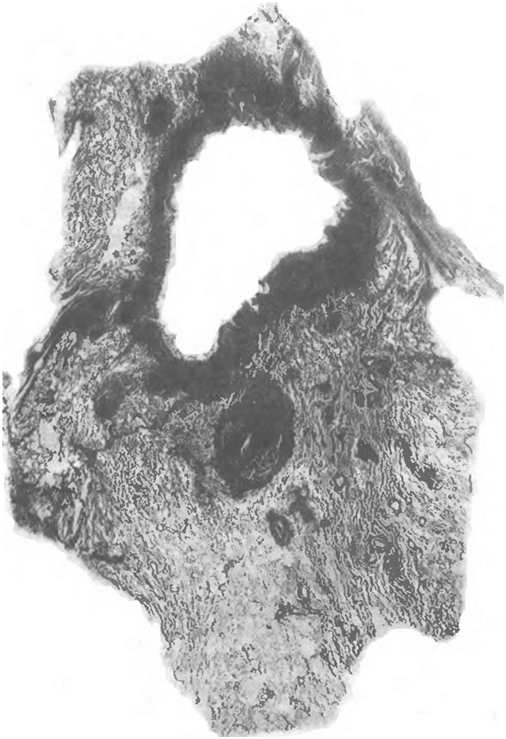

легкого, в периваскулярной или перибронхиальной ткани. Некоторые из них располагаются непосредственно в стенке кровеносных сосудов. Вокруг очагов обычно развивается эмфизема. В поздние фазы процесса развивается интерстициальный сетчатый склероз, особенно выраженный в верхних отделах легкого. В последних наряду с поражением интерстициальной ткани наблюдается образование массивных фиброзных рубцов на месте бывших туберкулезных очагов. В легочной ткани на фоне эмфиземы и фиброзных изменений могут быть инкапсулированные казеозные очаги, четко отграниченные от окружающей ткани (рис. 1.5).

Очаги располагаются среди фиброзированной стромы легкого, утолщенной плевры и междольковых перегородок, что указывает на их лимфогенный генез [Штефко В. Г., 1936; Иванова М. Г., 1939] (рис. 1.6). Одни очаги характеризуются хорошо выраженной капсулой, бедной клеточными элементами, и уплотненным казеозом, иногда даже частично фиброзированным; другие очаги более «свежие», казеоз в них окружен зоной из макрофагов, эпителиоидных и лимфоидных клеток с гигантскими клетками между ними. Капсула вокруг таких очагов выражена слабо, фиброзные волокна в ней инфильтрированы лимфоидными клетками. Рядом могут располагаться совсем «свежие» казеозные очаги, окруженные широкой клеточной зоной. Лимфоцитарная инфильтрация в таких очагах без четкой границы переходит на окружающую ткань.